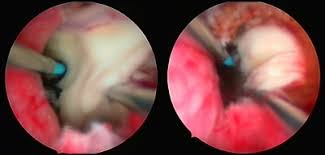

Prostatitis Prostataentzundung